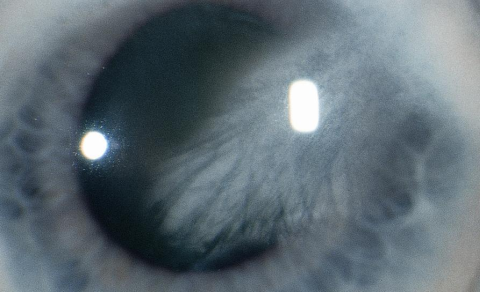

Primary LK may be peripheral, central, or diffuse. The disease is usually bilateral, and the central lipid, often with cholesterol crystals, may severely decrease visual acuity. Secondary LK features are dependent on the underlying cause but frequently one can find a characteristic dense yellow-white infiltrate associated with the presence of an adjacent corneal blood vessel.